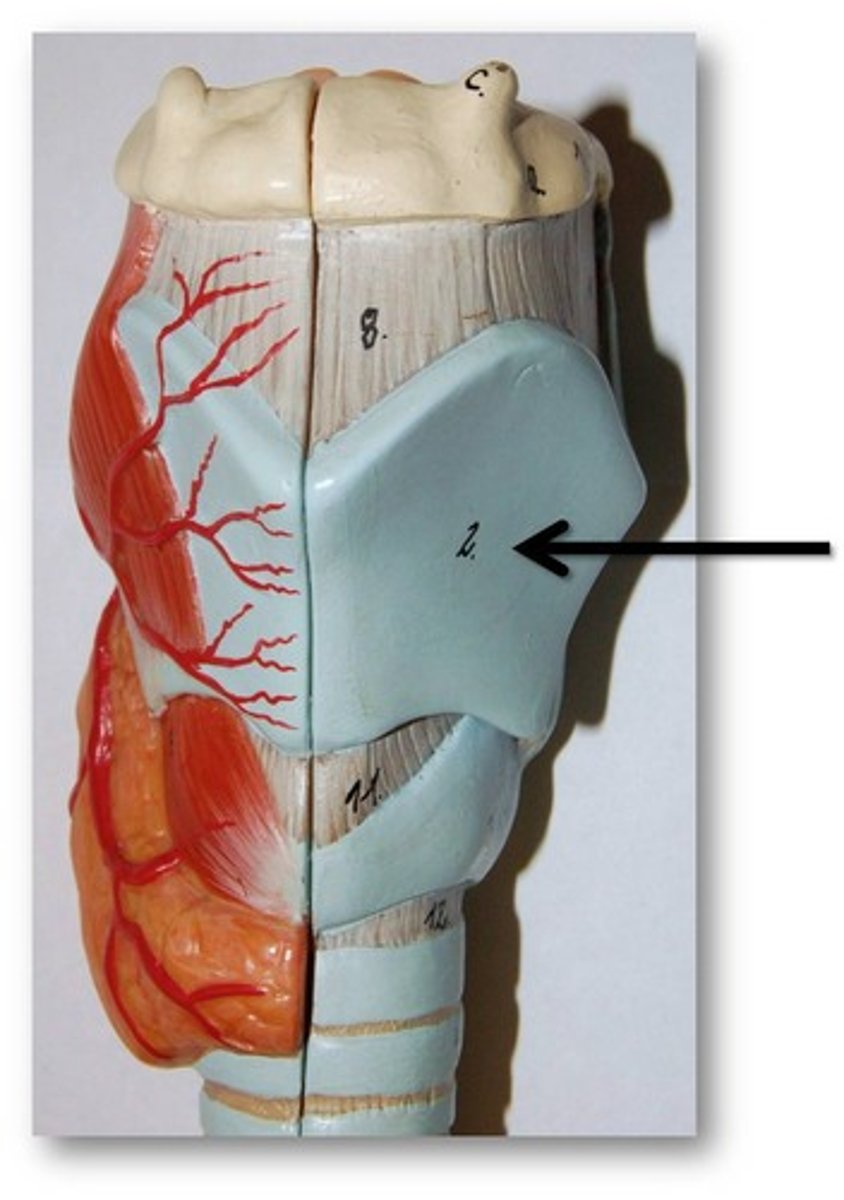

Laryngeal Cartilages

Largely construct the larynx (voice box)

Thyroid Cartilage

A firm prominence of cartilage that forms the upper part of the larynx; the Adam's apple

Cricoid Cartilage

The ring-shaped structure that forms the lower portion of the larynx

Larynx

Voice box; passageway for air moving from pharynx to trachea; contains vocal cords